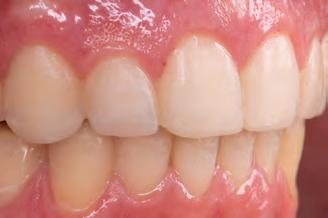

A 31-year-old woman presented with cosmetic concerns regarding her smile and requested a conservative enhancement. After clinical and radiographic analysis, digital 35mm photographs were taken and reviewed by the restorative clinician, technician, and surgeon (Fig 1). A digital impression was taken of the maxillary and mandibular arches using an intraoral scanner (Trios 3, 3Shape; Fig 2), and a smile design was developed with NemoSmile Design 3D software (Nemotec; Fig 3a). This allows for a facially driven smile frame to be created using reference lines of facial and smile proportions and natural teeth shapes and textures from the digital library (Fig 3b).

After developing the simulated mock-up, a 3D-printed resin model was created using CAD software (Fig 4a), and a clear PVS matrix (Exaclear, GC America) was fabricated to replicate the printed diagnostic wax-up using a nonperforated tray (Fig

4b). This matrix was used to create an intraoral motivational mock-up with bis-acryl composite (Luxatemp Ultra, DMG). This additive mock-up provides the interdisciplinary team with an intraoral translation for evaluation (Fig 5). Upon evaluation of the digital smile frame and the clinical translation, it was determined that multiple esthetic and restorative requirements were necessary for an optimal biologic framework, and the interdisciplinary team determined the best sequence for these procedures. The patient was presented with the interdisciplinary treatment possibilities that included restoring the maxillary anterior teeth and premolars with a minimally

invasive preparationless procedure or with less conservative veneer preparations. The restorative materials discussed included injectable resin composites and ceramic (ie, feldspathic, pressable, machinable). For an optimal biologic framework and health, it was determined that connective tissue grafting would be necessary for treatment of the recessiontype defects on the maxillary left central and lateral incisors, canine, and premolars. The patient opted for the conservative preparationless composite veneers using the injectable resin technique followed by a connective tissue surgical procedure using the tunneling technique.